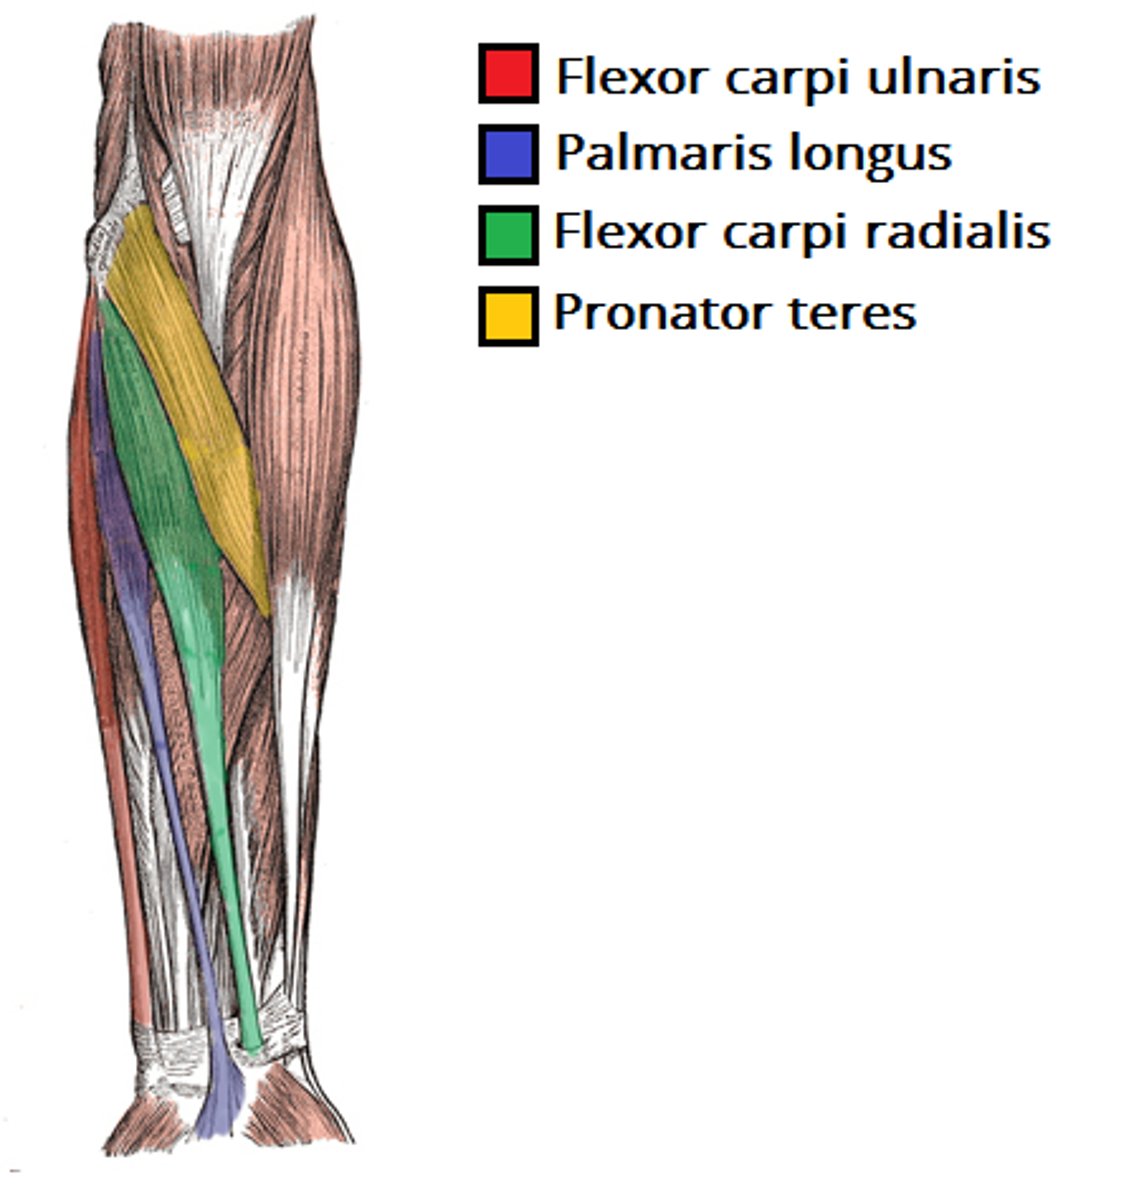

(Muscles of anterior compartment of the forearm (Flexors):) Superficial (1st) layer

Superficial (1st) layer: all muscles cross the elbow joint

-Pronator teres

-Flexor carpi radialis (FCR)

-Palmaris longus

-Flexor carpi ulnaris (FCU)

(Superficial (1st) layer:) Pronator teres

-Pronates forearm and flexes elbow

-Median n. (C5 - T1)

-Most lateral of this layer

(Superficial (1st) layer:) Flexor carpi radialis (FCR)

-Flexes and abducts hand

-Median n. (C5 - T1)

-Medial to pronator teres m.

(Superficial (1st) layer:) Palmaris longus

-Flexes hand and tenses palmar aponeurosis

-Median n. (C5 - T1)

-Medial to flexor carpi radialis m.

(Superficial (1st) layer:) Flexor carpi ulnaris (FCU)

-Flexes and adducts hand

-Ulnar n. (C7 - T1)

-Medial to palmaris longus m.